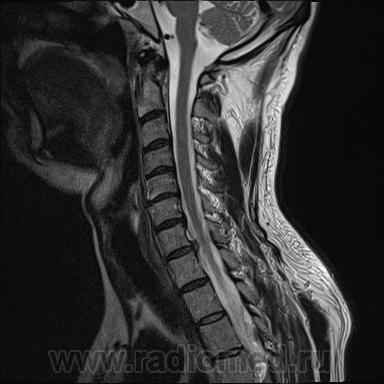

Грыжа диска. А где аксиалы?

Шейный остеохондроз.Грыжа С7-Th1.Не исключено наличие миелопатии на этом уровне, но боюсь ошибиться-изображения мелковаты ,идаже кажется, что есть повышение МРС от спинного мозга по Т1( скорее всего-артефакты?).

Левосторонняя парамедианная с компрессией корешка.

а это не перидурит??? смотрели месяц назад (в начале заболевания) было меньше.

Посмотрите на STIRе. Если жидкости нет, то простая грыжа. На этих сканах вообще-то жидкости не видно. За месяц грыжа могла и подрасти, смотря как лечили.

По-моему, только грыжа.

У меня такое мнение, хотя я не лучевик. Там из центра к правому краю рост бяки, возможно неври- или менинги- ома.